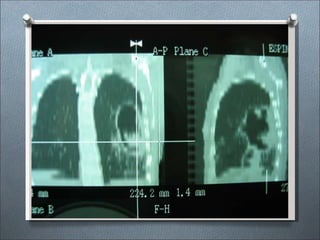

Radiología pulmonar:

• Nódulos solitarios subpleurales

• Lesiones en masa circunscritas

• Infiltrado neumónico difuso con cavidades

• Milia

• Derrame pleural

• Linfadenopatías

CRIPTOCOCOSIS RADIOLOGÍA